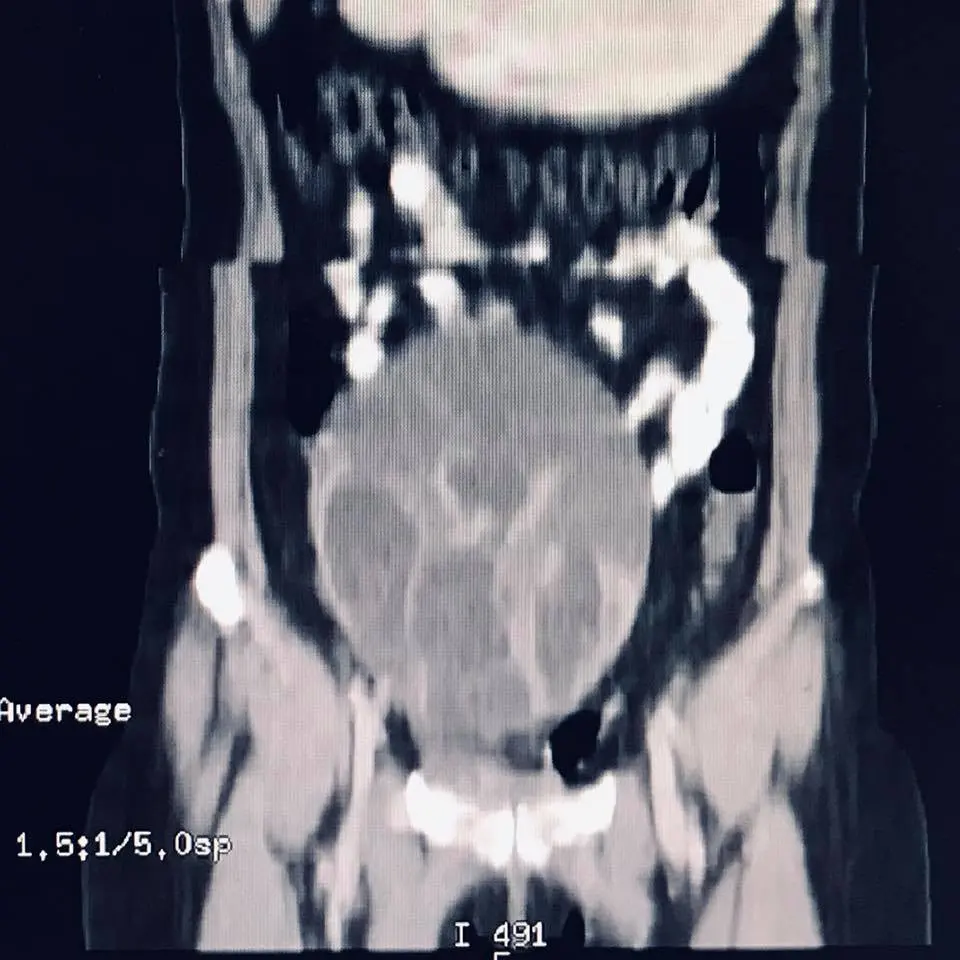

ทำไมวันนี้ถึงโตเบ้อเริ่มเลยหล่ะ_ผมจึงขอคิวด่วนกับรังสีแพทย์เพื่อตรวจเอ็กซ์เรย์คอมพิวเตอร์ : สรุปว่าผู้ป่วยมีถุงน้ำรังไข่โตขึ้นมาก จาก4ซม. เป็น 12.5 x 9.5 ซม. ในช่วงเวลาสองเดือนเองนะครับ

ผลการตรวจเอ็กซ์เรย์คอมพิวเตอร์_พบว่าถุงน้ำนี้กดเบียดท่อไตด้านขวาด้วยครับ ตอนนี้ไตด้านขวาของผู้ป่วยบวมมากเนื่องจากปัสสาวะไหลมาทางท่อไตไม่ได้แล้ว จึงทำให้ปัสสาวะคั่งค้างในไต

จากภาพเป็นถุงน้ำรังไข่ชนิดที่เรียกว่า มิวซินนัส (mucinous) ครับ เกิดขึ้นมาจากเยื่อบุผิวของรังไข่ ลักษณะภายนอกมักเป็นถุงน้ำขนาดใหญ่ ภายในประกอบด้วยถุงนำ้หลายถุง ผิวเรียบ ผนังหนาขุ่น ภายในถุงน้ำบรรจุน้ำเมือกเหนียว ส่วนใหญ่จะพบแค่ข้างเดียว